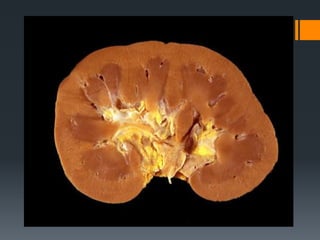

Kidneys Bean-shaped organ locatedbetween the 12th thoracic and 3rd lumbar vertebrae in the flank area Divided into the cortex (outer layer) and medulla (middle portion) Concave border has a notch called the hilum where the renal artery, vein, nerves and lymphatic vessels enter. The ureter starts at the hilum Contains the nephrons (functional units of the kidney)

Divided into the cortex (outer layer) and medulla

(middle portion)